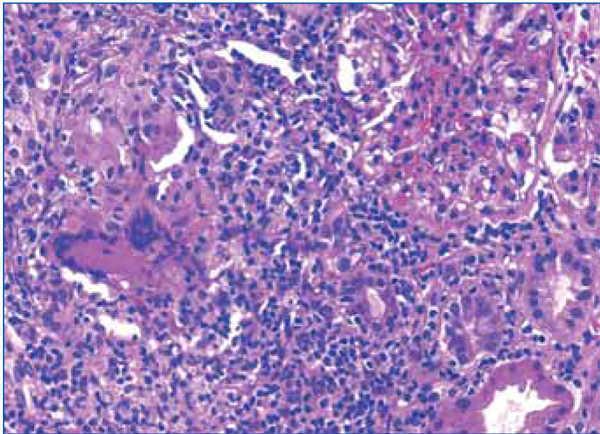

A cervical adenopathy biopsy was performed in which epithelioid granulomatous inflammation was observed with extensive caseous necrosis (Figure 1). A few bacilli were observed in the Ziehl-Nielsen stain (Figure 2).

Given these findings, a fibrobronchoscopy was performed, which did not reveal any macroscopic lesions in the airway. Bronchoalveolar lavage showed a moderate amount of lymphocytes. Bronchial lavage was negative and a transbronchial fine needle aspiration of a mediastinal adenopathy identified granulomas. Ziehl stain was initially reported as negative, but a second observation noted a single acid-alcohol resistant bacillus. After fibrobronchoscopy, a gamma interferon release assay for tuberculosis (QuantiFERON®) was performed, which was positive. Based on these tests, a decision was made to start treatment for tuberculosis.

Given the clinical (severe renal failure), radiological (kidneys of normal size and echostructure) and laboratory findings (anaemia, proteinuria and microscopic haematuria), a renal biopsy was performed in which interstitial inflammation at the expense of lymphocytes was detected, accompanied by histiocytes, which formed granulomas at several points (Figure 2 and 3). One of these contained multinucleated Langhans giant cells. Glomeruli were normal. Granular material occupied the tubules and the epithelium was flattened. There were no microorganisms in the PAS or Ziehl-Nielsen stain.

Figure 1. Extensive caseous necrosis foci in the right supraclavicular lymph node biopsy

Figure 2. Detection of a bacillus in the Ziehl-Nielsen stain of the lymph node biopsy

Figure 3. Interstitial lymphocytic infiltrate and epithelioid granuloma in the renal biopsy

Figure 4. Detail of the interstitial infiltrate